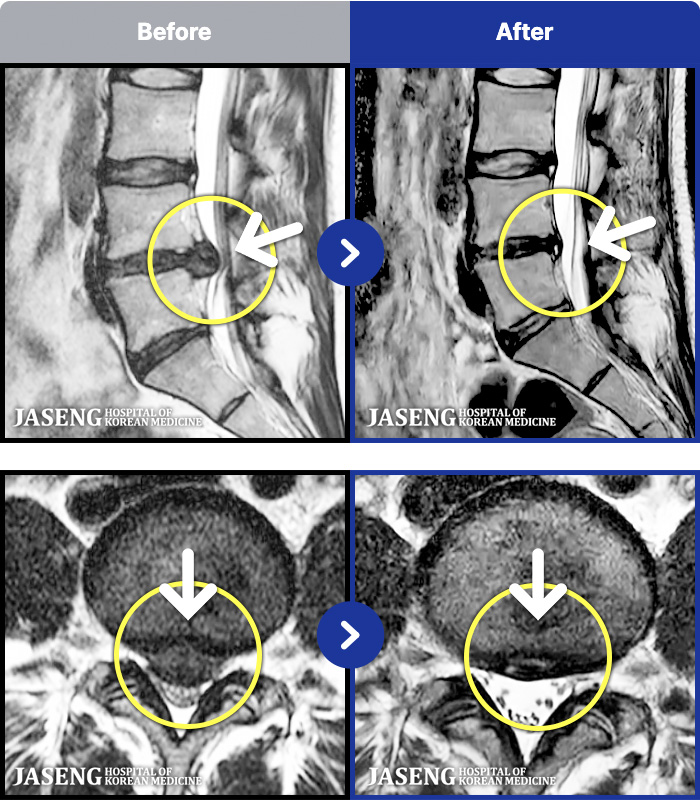

MRI ġ

1,304 MRI ũ ʸ Ȯϼ.